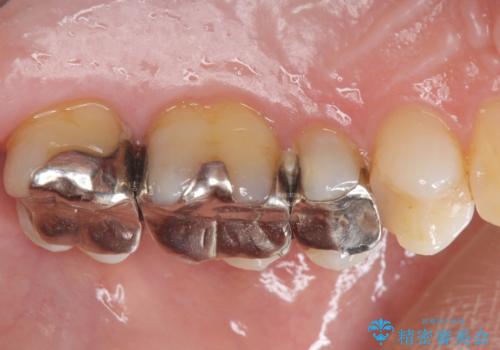

- 長年気になっていた銀歯を全て除去したい、とメタルフリー治療を希望され来院されました。

銀歯を丁寧に除去すると、銀歯の下で虫歯の再発やセメントの劣化が確認されたので、拡大鏡・マイクロスコープを用いて虫歯のみを丁寧に取り除いたのち、精密なセラミッククラウンの製作を進めます。